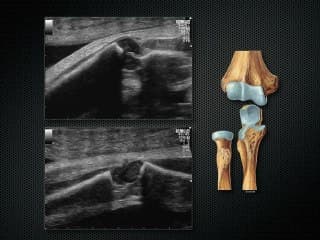

Vous y trouverez des conférences présentées lors des congrès nationaux et internationaux, des cours magistraux dispensés par des experts reconnus, des démonstrations pratiques sur des cas cliniques réels, ainsi que des podcasts et tables rondes sur les dernières avancées de la spécialité.

Cette ressource est destinée aux médecins échographistes, sages-femmes, internes et à tous les professionnels de santé impliqués dans le suivi échographique de la grossesse. L'accès à la médiathèque est réservé aux membres du CFEF.